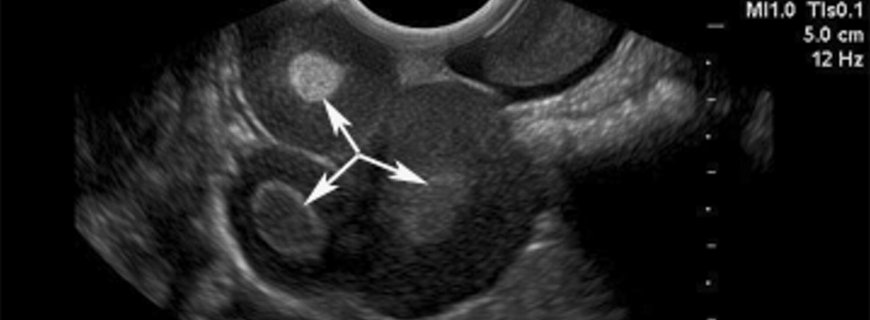

Tıbbi olarak sağlıklı, şüpheli yumurtalık kitlesi olan hastalarda ameliyatla değerlendirme yapmak gereklidir. Kabul edilebilir büyüklükteki kitlelerde (genellikle 8-10 cm ve daha küçük), karın içinde sıvı veya uzak bölgelerde hastalık yoksa laparoskopik değerlendirme kabul edilebilir. Şüpheli yumurtalığın ameliyat sırasında patolojik değerlendirmesi sağlanmalıdır. Bulgular yüksek olasılıkla yumurtalık kanserini telkin ediyorsa jinekolojik onkoloji konusunda uzman bir cerrahın çağırılması daha uygun olacaktır.